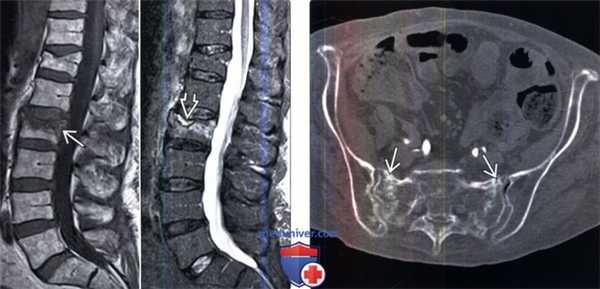

(Слева) На сагиттальном КТ-срезе и рентгенограмме в боковой проекции визуализируется остеопоротический перелом тела среднегрудного позвонка.

(Справа) На сагиттальном STIR МР-И отмечается гиперинтенсивность сигнала тела среднегрудного позвонка, связанная с отеком костного мозга на фоне свежего остеопоротического компрессионного перелома. На Т1-ВИ определяется гипоинтенсивность сигнала и низкоинтенсивная полоса, представляющая собой линию перелома. Негомогенная ИС в Т1/Т2/STIR-режимах и неполное замещение костного мозга являются характерными признаками доброкачественного характера перелома.

(Слева) Сагиттальный срез, Т1-ВИ: гипоинтенсивность сигнала, ориентированная параллельно замы-кательной пластинке. На сагиттальном STIR МР-И отмечается гиперинтенсивность сигнала в этой же области и симптом жидкости. Симптом жидкости чаще наблюдается при свежих доброкачественных остеопоротических переломах. Остеопороз и минимальная травма приводят к остеонекрозу в области поврежденной замыкательной пластинки. В зону остеонекроза «продавливается» жидкость, что становится причиной появления МР-симптома «жидкости».

(Справа) Аксиальный КТ -срез: признаки двустороннего остеопоротического перелома крестца. У 2/3 пациентов в таких случаях не удается установить факта травмы либо травма эта оказывается минимальной.